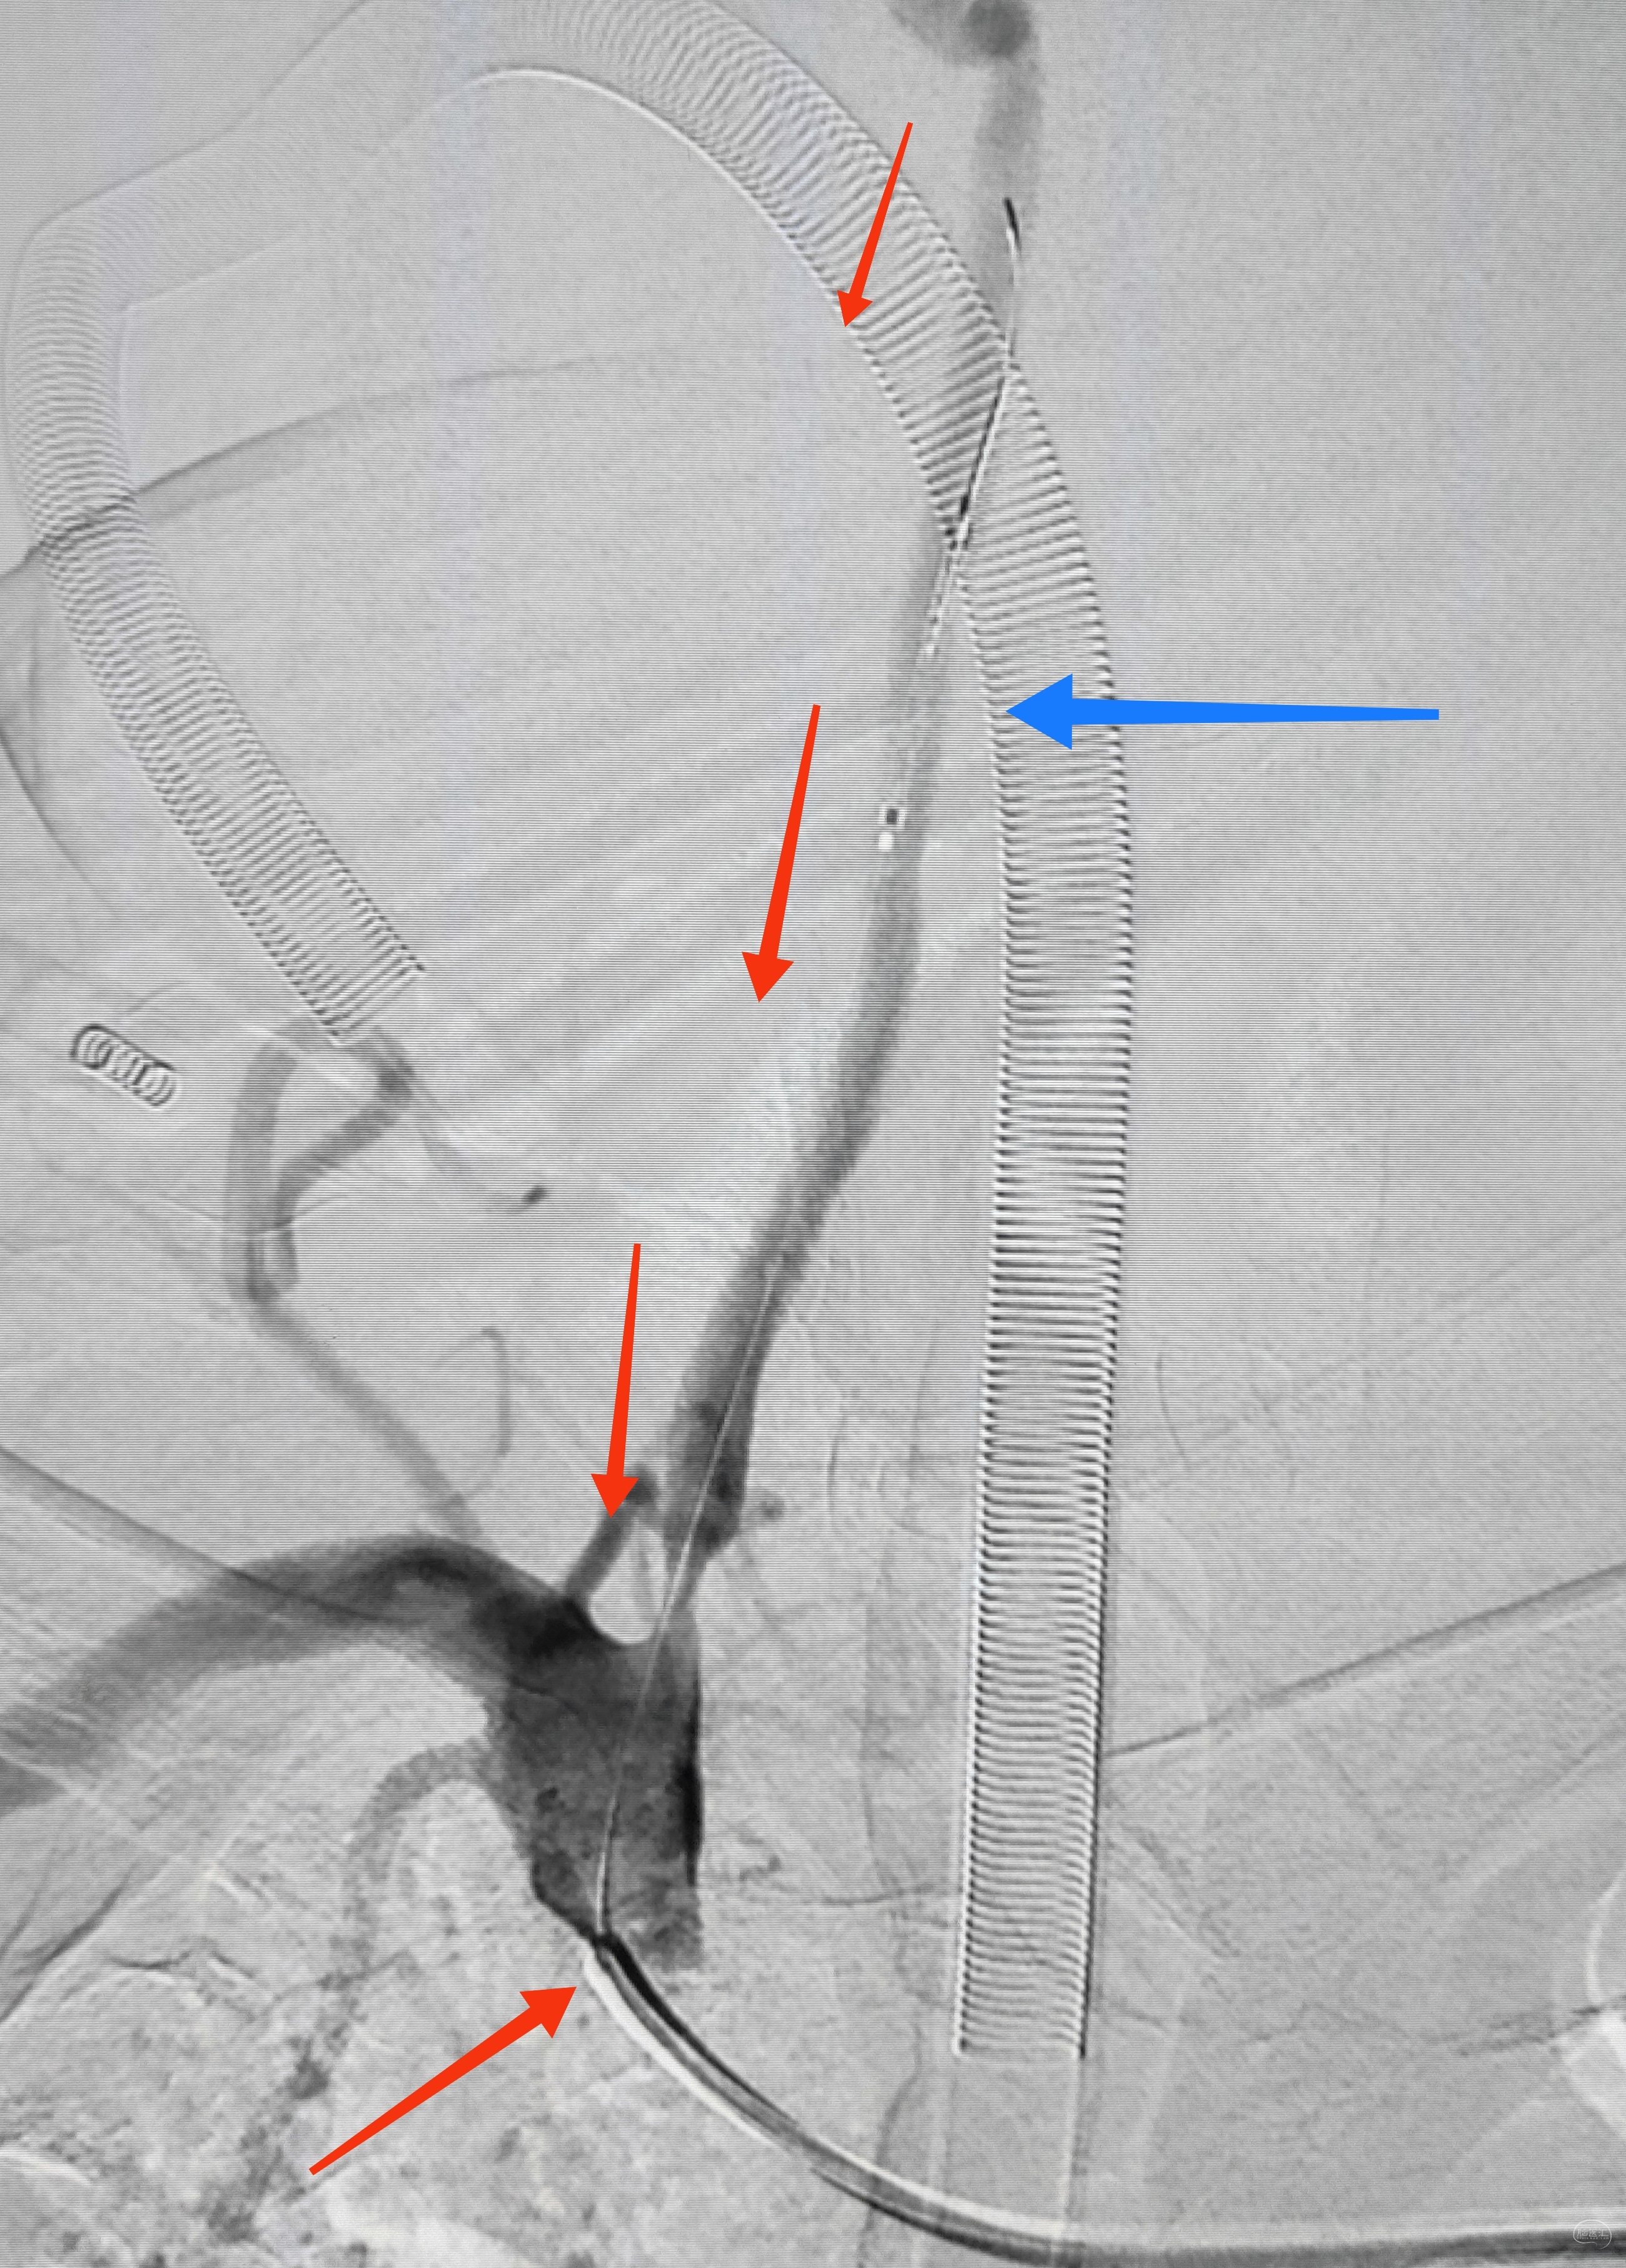

因为是极重度狭窄,支架前拟小球囊预扩,谨慎起见,置入泰杰Proender保护伞并打开,以免不测

梯度预扩,先雅培1.5×15小球囊预扩

再Sino3×20球囊预扩

预扩满意,保护伞不浪费,借助保护伞的支撑和保护作用,上送导引导管(不怕掉斑块,物尽其用),为颅内狭窄处理提供更佳支撑

看图说话,没啥聊的。球囊不浪费,Sino3×20球囊预扩V4狭窄

EP4.5×22支架置入

导引导管保持原位,导管内安全输送Herculink5×20,通过椎开口狭窄并走远,再回撤导引导管至锁骨下动脉

球扩支架顺利释放

术后即刻造影,右侧椎动脉显影佳,并向左侧前循环代偿供血良好